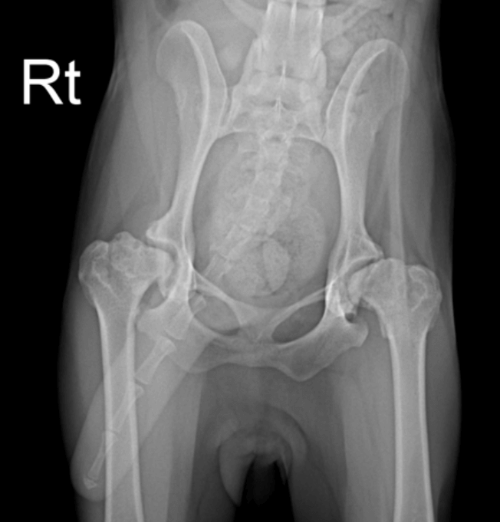

- 고관절 엑스레이: 고관절 이형성증은 고관절의 방사선 촬영을 통해 가장 잘 진단됩니다. 이를 통해 질병의 진행정도와 퇴행성 관절염 등 뼈의 변형을 확인할 수 있습니다. 촬영 자세가 엄청난 통증을 수반하기 때문에 가벼운 진정이 필요할 수 있습니다.